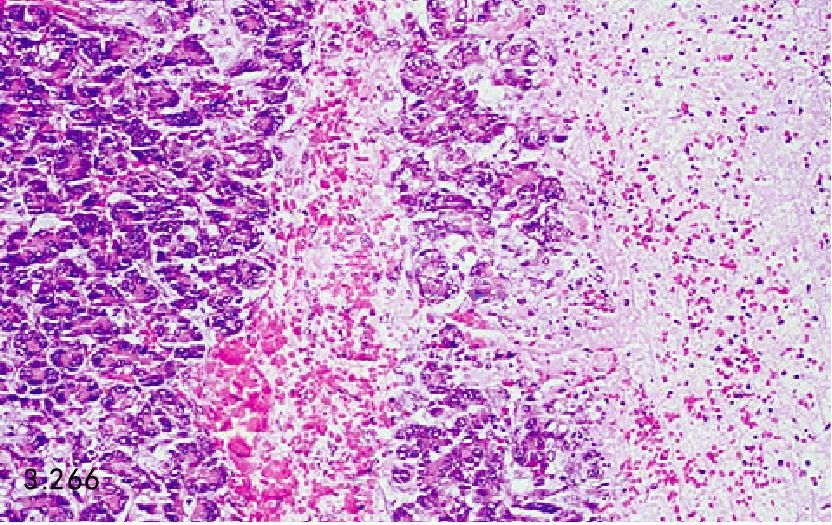

图3.265和图3.266 上图患犬胰腺的组织病理学图片显示为腺体坏死、出血、水肿,由中性粒细胞和巨嗜细胞的炎性浸润(H&E)。